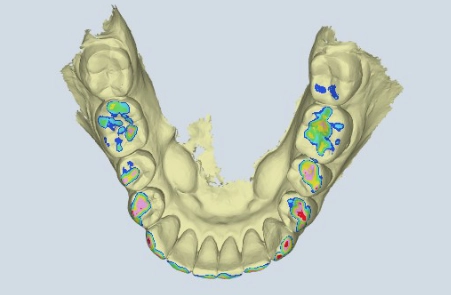

Wir nutzen modernste Technologien, um Kieferbewegungen und Biss in Echtzeit zu analysieren – so können wir Behandlungen planen, die nicht nur großartig aussehen, sondern sich auch richtig anfühlen.

Digitale CMD-Analyse

Wir nutzen Kiefertracking und 3D-Bildgebung, um das Zusammenspiel von Gelenken, Zähnen und Muskeln sichtbar zu machen.

Von digitalen Scans bis zu handgefertigten Alignern – wir vereinen Präzision, Sorgfalt und Erfahrung in jeder Phase Ihrer kieferorthopädischen Behandlung